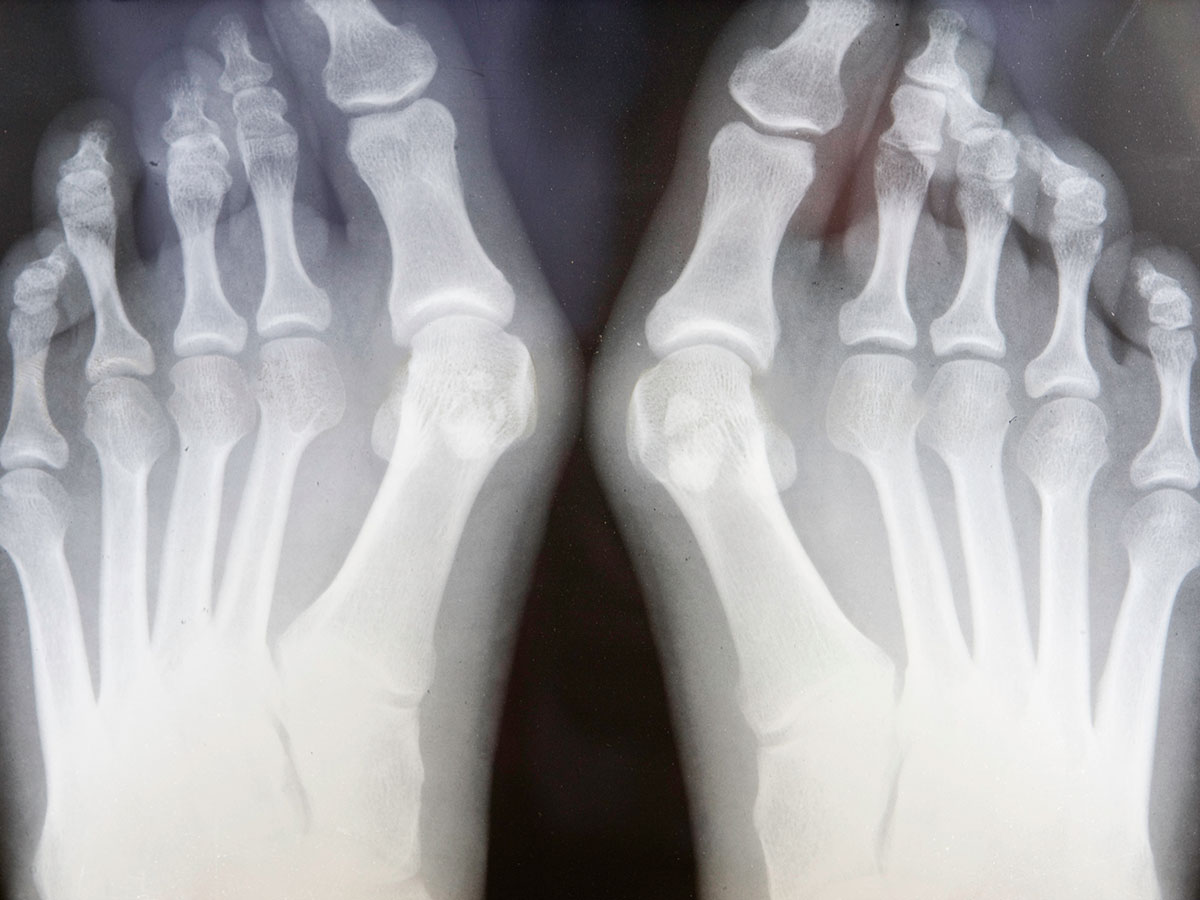

Выявляется болезнь либо визуально (когда нарост достигнет довольно больших размеров), либо случайно при проведении рентгенологической диагностики других заболеваний. Окончательный диагноз при экзостозе устанавливается только с помощью рентгена.

Обратите внимание: при определении размера и формы опухоли нельзя забывать о том, что на снимке видна только костная часть нароста, а хрящевая ткань не определяется. Поэтому истинный размер новообразования будет отличаться от изображенного на рентгеновском снимке в большую сторону.

Симптомы и диагностика наростов на костях

Экзостоз можно выявить во время осмотра и ощупывания подозрительных участков на стопе, голени, руке, ключицах. Недуг развивается постепенно и может никак себя не проявлять в течение долгого времени. Болевые ощущения могут появиться лишь тогда, когда нарост будет давить на ближайший сосуд или нерв. Иногда костяные и хрящевые наросты обнаруживаются случайно, во время рентгена. Рентгеновское обследование дает развернутую информацию о виде и форме нароста, о его размерах степени развития. Нужно помнить, что на снимке рентгена хрящевой ткани новообразования не видно. Из-за этого нарост на фото всегда меньше, нежели в реальности.